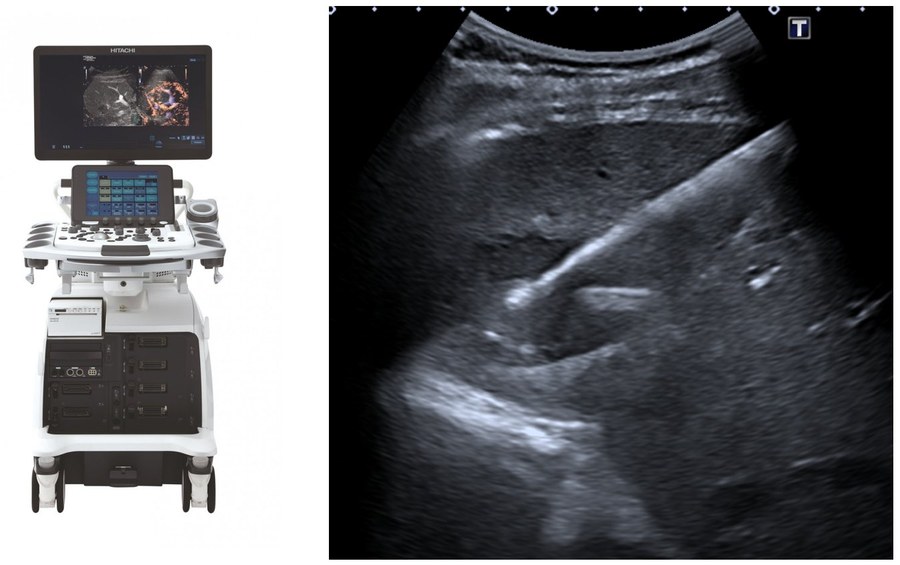

Notre plateau technique comprend un bloc opératoire dédié avec salles d'angiographie, un scanner interventionnel avec arceau robotisé, et des échographes haute gamme équipés de fusion IRM/scanner/cone-beam CT pour la précision maximale.